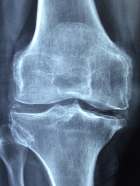

무릎 퇴행성관절염 증상 원인 관리방법 등 무릎 퇴행성관절염 정보에 대해 알아보도록 하겠습니다. 무릎 퇴행성 관절염은 무릎 관절의 연골이 닳아 없어지면서 발생하는 질환입니다. 연골이 없어지면 뼈가 서로 마찰하고 자극을 받아 통증과 염증이 생깁니다.

무릎 퇴행성 관절염의 진단은 환자의 병력과 증상을 파악하고 방사선 검사, MRI 검사, 동위 원소 검사, 관절경 검사 등을 통해 할 수 있습니다. 방사선 검사는 연골의 손실과 골극의 형성을 확인할 수 있습니다. MRI 검사는 연부 조직과 반월판의 손상을 확인할 수 있습니다. 동위 원소 검사는 관절의 혈류와 골 형성의 활성도를 확인할 수 있습니다. 관절경 검사는 관절 내부의 상태를 직접 관찰할 수 있습니다.